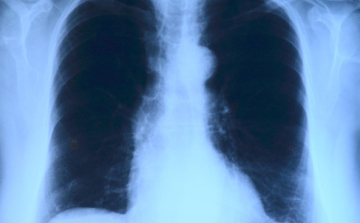

Elvégezték az országban az első tüdőverőér-tágítást

Az országban elsőként a Debreceni Egyetem Klinikai Központjában végeztek tüdőverőér-tágítást - közölte a felsőoktatási intézmény sajtóirodája kedden az MTI-vel.